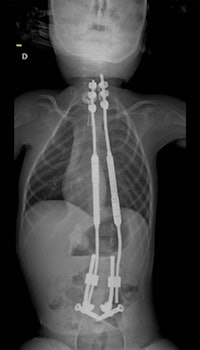

Surgeons in France used a 3D-printed model of the spine to simulate and hone a new robot-guided procedure on a 6-year-old boy with severe scoliosis. The young patient had such a severe combination of progressive scoliosis and spinal muscular atrophy (a neuromuscular disorder) that he was unable even to sit down.

Simulating the surgery on a 3D-printed model ultimately decreased actual operation time and minimized the risk of complications, according to the group. The success of the procedure helped prevent the onset of potential complications of scoliosis and also allowed the child to sit comfortably for the first time. The actual surgery took place on 28 September.